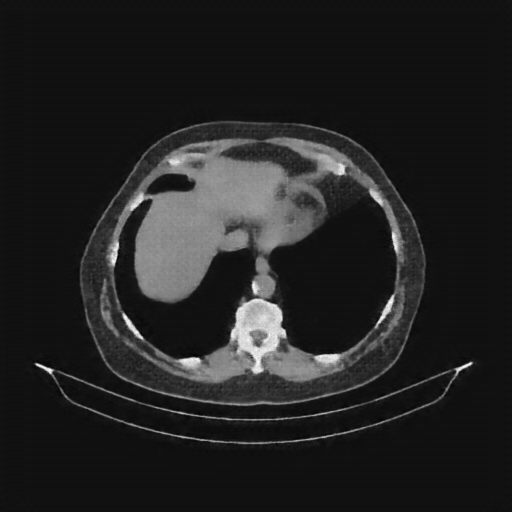

Reconstructed NATIVE CT scan (cycle consistency)

Full window (WL 1023.5, WW 4095 β†’ Low βˆ’1024, High +3071)

Actual HU range: [-863.7, 702.5]

Lung window (WL -600, WW 1500 β†’ Low βˆ’1350, High +150)

Actual HU range: [-863.7, 150.0]

Mediastinum window (WL 40, WW 400 β†’ Low βˆ’160, High +240)

Actual HU range: [-160.0, 240.0]